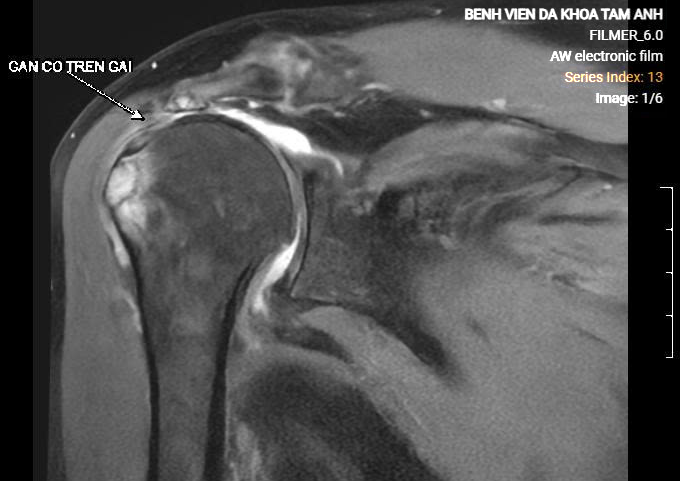

BS.CKII Nguyễn Ngọc Tiệp, khoa Chấn thương Chỉnh hình, Bệnh viện Đa khoa Tâm Anh Hà Nội, cho biết kết quả chụp MRI khớp vai bà Vân ghi nhận gân cơ dưới gai đứt bán phần, gân cơ trên gai đứt hoàn toàn, teo mỡ, đầu gân co rút sâu vào trong 4 cm so với điểm bám. Các gân cơ chóp xoay khác viêm, phù nề.

Hệ cơ vai gồm 4 gân: trên gai, dưới gai, dưới vai và tròn bé. Trong đó, cơ trên vai có vai trò khởi đầu động tác nâng và dang cánh tay, còn cơ dưới gai giúp xoay cánh tay. Bác sĩ Tiệp cho biết gân trên gai đứt lâu ngày khiến chỏm xương cánh tay bà Vân không còn được giữ vững ở vị trí trung tâm ổ chảo, dần di lệch lên trên, gây hẹp khoang dưới mỏm cùng vai, chèn ép các cấu trúc phần mềm xung quanh gây đau, thoái hóa khớp sớm. Người bệnh chủ yếu đau ban đêm và buổi sáng vì khi ngủ trở mình, khớp vai di lệch, chèn ép nhiều.